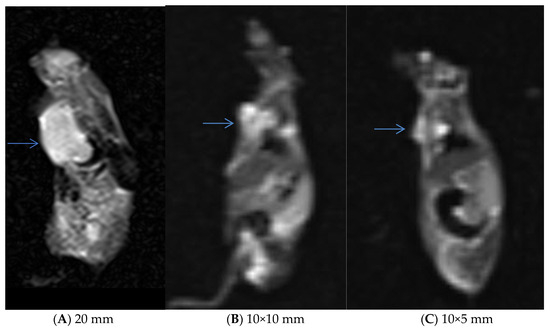

3.5. In Vivo Experiments and MRI Analysis